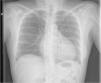

Paciente de 47 años con derrame pericárdico